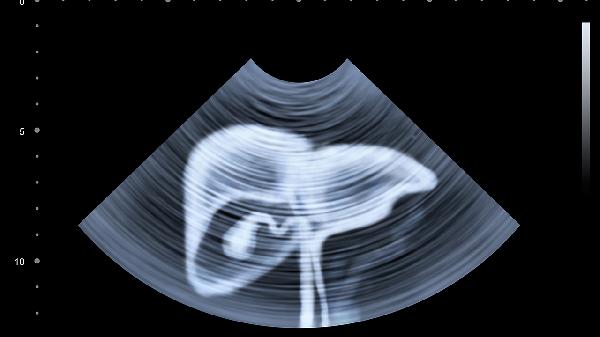

慢性膽囊炎可能與膽囊結石、細菌感染等因素有關,通常表現為右上腹隱痛、右肩背部放射痛、進食油膩食物后加重等癥狀。這種情況可遵醫(yī)囑使用消炎利膽片、熊去氧膽酸片、頭孢克肟分散片等藥物。患者平時應保持低脂飲食,適當控制體重,定期復查腹部超聲。